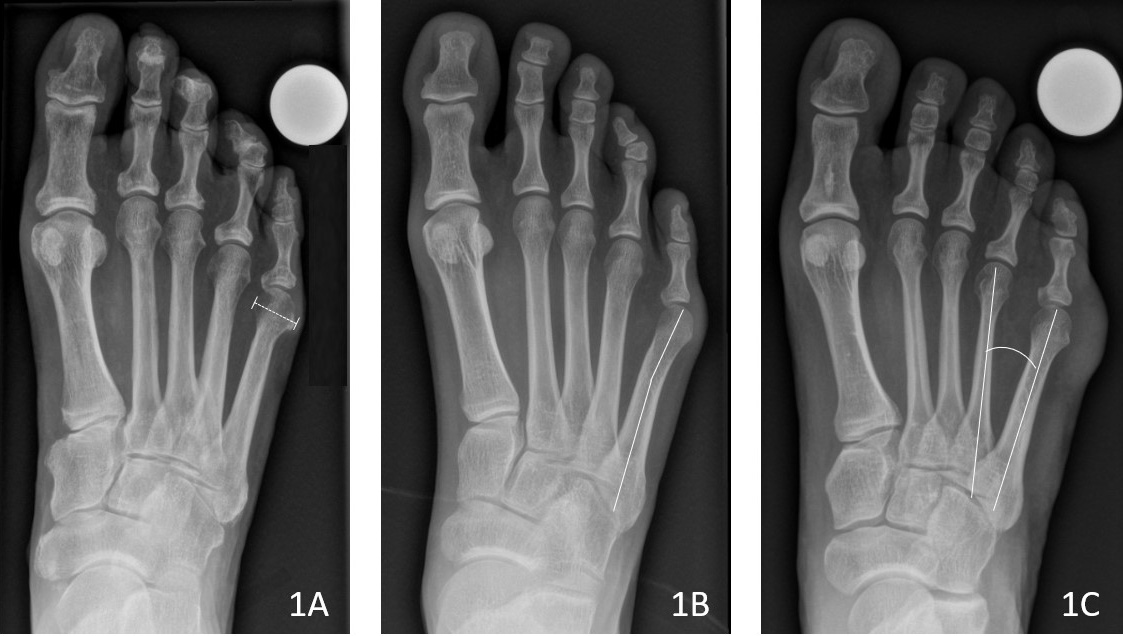

Radiologisch unterscheidbare Deformitätstypen *

| Typ I | Vergrösserter Durchmesser des fünften Mittelfussköpfchens (vgl. Bild unten 1A). |

| Typ II | Abbiegung des fünften Mittelfussknochens nach aussen (vgl. Bild unten 1B). |

| Typ III | Vergrösserter Winkel zwischen dem vierten und fünften Mittelfussknochen (vgl. Bild unten 1C). |

Bild: Universitätsklinik Balgrist